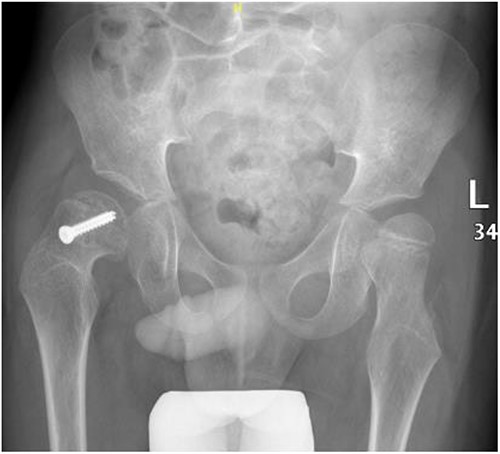

A 5-year-old independent ambulatory Middle Eastern boy with CP who was born preterm and developed grade III intraventricular haemorrhage and periventricular leucomalacia and was on AEDs, including valproic acid (VPA) and levetiracetam (LEV), for >3 years and was controlled over the last year (no history of seizure attack) presented to the emergency room (ER) with right hip pain and inability to bear weight for 4 weeks; the patient had no history of fever or trauma. Physical examination shows a thin, the weight is 12 kg, the height is 101 cm, vital signs within the normal range, tenderness over the right hip, and external rotation of the right hip, with restricted hip mobility. A radiological study was performed ~3 months before the patient presented to the ER for follow-up examination of a left hip coxa valgus deformity with no apparent abnormalities in the right hip (Fig. 1). Initial imaging studies conducted in the ER showed an anterior–posterior view of the pelvic radiograph, revealing Klein’s line [13] not intersecting the capital femoral epiphysis (Fig. 2), and frog-leg lateral view radiograph of the right hip (Fig. 3) confirmed SCFE and Southwick’s slip angle [13] of ~50° (moderate). Laboratory findings were clear for endocrine and renal diseases or infection, except for low vitamin D (total 25-OH Vitamin D: 43.4 nmol/L), suggesting vitamin D insufficiency. The diagnosis was confirmed with clinical and radiological studies as right-sided unstable SCFE requiring surgery. Surgical intervention was performed with percutaneous in situ fixation using a single fully threaded 4.5-mm cannulated screw (Fig. 4). Postsurgical rehabilitation included non-weight-bearing right lower extremities for 6 weeks. Regular follow-up with serial radiology studies showed stable fixation with no migration of screw or further slippage at 6 weeks (Fig. 5) and 3 (Fig. 6), 15 (Fig. 7), and 36 months (Fig. 8). During follow-up, a painless range of motion in the right hip was observed, with full weight-bearing and resumption of his usual activities with no complaints.

Pelvic anterior–posterior radiograph, 3 months following post-operative fixation.